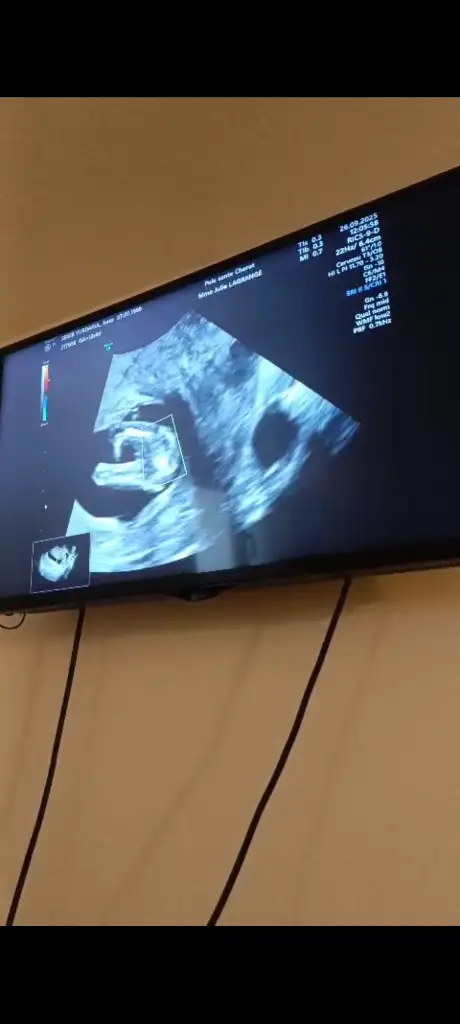

A ayla112 Üye Kayıtlı Üye 4 Haziran 2024 82 7 6 27 26 Eylül 2025 Konu Sahibi Konu Sahibi ayla112 #1 Kizlarrr 12+6 haftalık hamileyim tahmin edebilir misinizzzz Eklentiler 1000017983.webp 14,1 KB · Görüntüleme: 50 1000017977.webp 32,6 KB · Görüntüleme: 51 1000017953.webp 12,6 KB · Görüntüleme: 50

K kivircikbyn Üye Kayıtlı Üye 31 Ekim 2024 85 21 8 25 14 Ekim 2025 Konu Sahibi Konu Sahibi ayla112 #2 ayla112 .!.: Kizlarrr 12+6 haftalık hamileyim tahmin edebilir misinizzzz Genişletmek için tıkla... Cinsiyetiniz neymiş benim bebeğimin de çıkıntısı bu şekilde ama

A ayla112 Üye Kayıtlı Üye 4 Haziran 2024 82 7 6 27 17 Ekim 2025 Konu Sahibi Konu Sahibi ayla112 #3 kivircikbyn .!.: Cinsiyetiniz neymiş benim bebeğimin de çıkıntısı bu şekilde ama Genişletmek için tıkla... Fransa'da yaşıyorum. Doktor cinsiyet öğrenmek için Kasım 27 ye verdi randevu o zaman anca 21-22 hafta olacağım siz öğrenebildinizmi